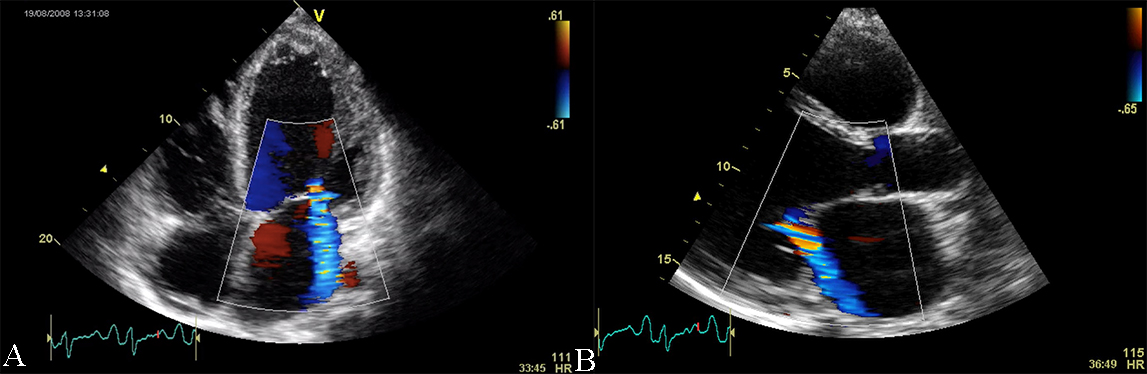

Fig. 3.Echocardiographic aspect of DCM in a patient with idiopathic dilated cardiomyopathy. (A) Apical 4 chamber view, showing dilated left ventricle, dilated left atrium, and significant secondary mitral regurgitation flow with Coanda effect. (B) Parasternal long-axis view, showing dilated left ventricle, dilated left atrium, and significant secondary mitral regurgitation flow with Coanda effect. An online video of this patient with idiopathic dilated cardiomyopathy is available (Appendix Video 2 and 3).

Color and spectral Doppler echocardiography is of limited use in the diagnosis

of DCM, except for atrioventricular valve incompetence. One constant feature is

the presence of mitral regurgitation, secondary to the annulus dilation with

abnormal leaflet tethering. Mitral regurgitation can present with different

degrees of severity and is an additional prognostic factor (see Fig. 3 and

Appendix Video 2 and 3). The pathophysiology of mitral regurgitation in DCM is usually

due to abnormal leaflet tethering mandated by the change in LV shape from

ellipsoid to spherical. As cardiomyopathy progresses, the point of leaflet

coaptation migrates from its normal basal location to a spot deeper in the LV

cavity this leading to also to an apposition defect with the generation of an

eccentric regurgitant jet. Moreover, DCM patients present with an abnormally low

diastolic function [5]. Restrictive or pseudo-normal diastolic inflow patterns

impact the patients with DCM, with an associated poor prognosis [10, 11]. The

assessment of the pulmonary vein flow signal as an adjunct to the mitral inflow

pattern is very important in the echographic evaluation of DCM. Abnormal

pulmonary venous systolic flow patterns have been shown to correlate with the

future development of pulmonary hypertension. Loss of the systolic dominant flow

pattern suggests elevated filling pressure and the difference between the

pulmonary venous flow reversal duration and the mitral inflow duration during

atrial contraction greater than 30 ms predicts mortality and hospitalization [9].

Studies evaluating diastolic compliance with Doppler echocardiography have shown

also an altered mitral diastolic flow with a short deceleration time